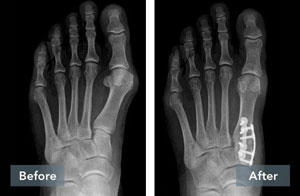

Lapiplasty® Before & After Results

The Positive Effect of Lapiplasty®

While traditional 2D osteotomy surgery merely cuts & shifts the bone to address the cosmetic bump, Lapiplasty® 3D Bunion Correction™ does more — it corrects the entire bone in 3D and secures the unstable foundation to get you back on your feet quickly in a walking boot. The Lapiplasty® Procedure has also shown low recurrence; 97% and 99% maintain 3D correction in 13 and 17 months respectively.